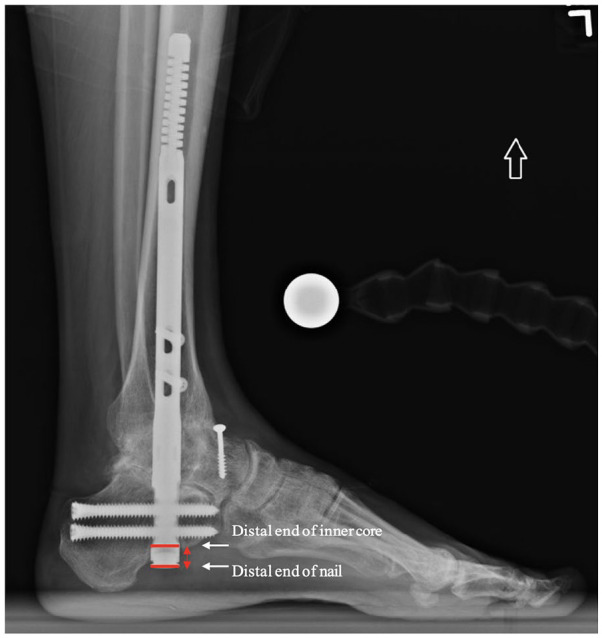

Methods: Inclusion criteria consisted of patients who had undergone a tibiocalcaneal or TTC arthrodesis using the Phantom Hindfoot TTC Nail System with at least 6 months of follow-up. Radiographic analysis evaluated for successful union and flexibility of the flex coil. Patients were monitored for postoperative complications and additional secondary procedures.

Results: Twenty-one patients were included and had an average follow-up of 9.4 ±4.7 months (range, 4.3-19 months). No intraoperative complications were reported. Seven patients experienced at least 1 adverse event, which included device migration, asymptomatic nonunion, symptomatic nonunion, bone stress reaction, device prominence, and screw breakage. There were no events of perioperative fractures or device breakage. Two patients required secondary surgical interventions. The 5 remaining patients were managed conservatively. An average nail coil flexion angle of 2.6 ± 3.1 degrees and 0.8 ± 1.59 degrees was found on lateral and anteroposterior radiographs, respectively. The overall union rate at a mean follow-up of 9.4 months was 90.4% (95% CI 69.6%, 98.8%).

Conclusion: TTC arthrodesis via the AC nail demonstrated similar union rates and outcomes at short-term follow-up compared with rates generally reported in the literature for other IM nail constructs. The AC nail was able to function as designed and allow for motion at the proximal bone-implant interface.